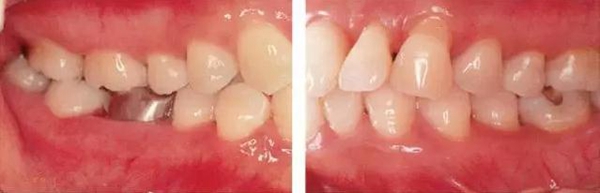

●45歲女性 慢性牙周炎(重度)口腔內(nèi)照片

45歲女性,曾經(jīng)接受過(guò)口腔衛(wèi)生指導(dǎo)和牙周治療,菌斑控制情況除去部分磨牙部位其余基本良好。牙周探診檢查結(jié)果為全頜牙周袋深4~6mm,同時(shí)X片檢查數(shù)據(jù)可看到全頜重度骨吸收。根據(jù)以上檢查數(shù)據(jù)可診斷出該患者為慢性牙周炎廣泛型(重度)。牙齦沒(méi)有嚴(yán)重浮腫,但可觀察到紅褐色腫脹。上頜前牙有前突。

●33歲男性 侵襲性牙周炎廣泛型口腔內(nèi)照片

33歲男性,吸煙(1天10根,12年吸煙史)。菌斑控制狀況不好,牙周探診全頜牙周袋深5~10mm之外,全頜性牙周袋出血,部分牙周袋有排膿現(xiàn)象。X片可觀察到全頜性重度骨吸收。通過(guò)以上檢查可診斷出該患者為侵襲性牙周炎廣泛型。視診可知牙齦雖然有炎癥,但沒(méi)有出現(xiàn)嚴(yán)重浮腫,沒(méi)有大量牙結(jié)石沉積。